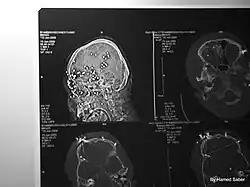

Use of kinetic-impact-projectiles

X-ray of an Iranian protestor who suffered eye damage after being shot in the face with a non-lethal stinger round in 2009

Kinetic-impact-projectiles (KIPs) also known as baton rounds, or rubber/plastic bullets are non-lethal projectiles used for crowd control purposes by riot police.[6][7][1] KIPs are marketed as non or less-lethal weapons used for the purposes of dispersing crowds without causing penetrating wounds.[6] However, when used inappropriately and fired indiscriminately, they have been known to cause injuries leading to life-long disability, or even death.[6][7][8] Examples of KIPs include rubber or plastic bullets, bean bag rounds, sponge rounds (rounds with a softer nose/tip to limit impact) or pellet rounds of birdshot or buckshot.[6][7] Abolfazl Adinezadeh, a 17 year old boy that had joined the Woman, Life, Freedom protests is one of many examples of protesters in Iran who have been killed as a result of close range discharge of KIPs.[8][9] Cases have also been reported in which protesters have either been killed, or lost an eye as a result of being hit directly by tear gas canisters.[7][10][11][12] Abolfazl Amirataie, a 16 year old boy who had joined protests on 22 September 2022 was shot directly in the head at close range with a tear gas canister, causing catastrophic damage to one side of his skull and brain.[10] After 8 months in a vegetative state, Amirataie succumbed to his injuries on 27 May 2023.[10]